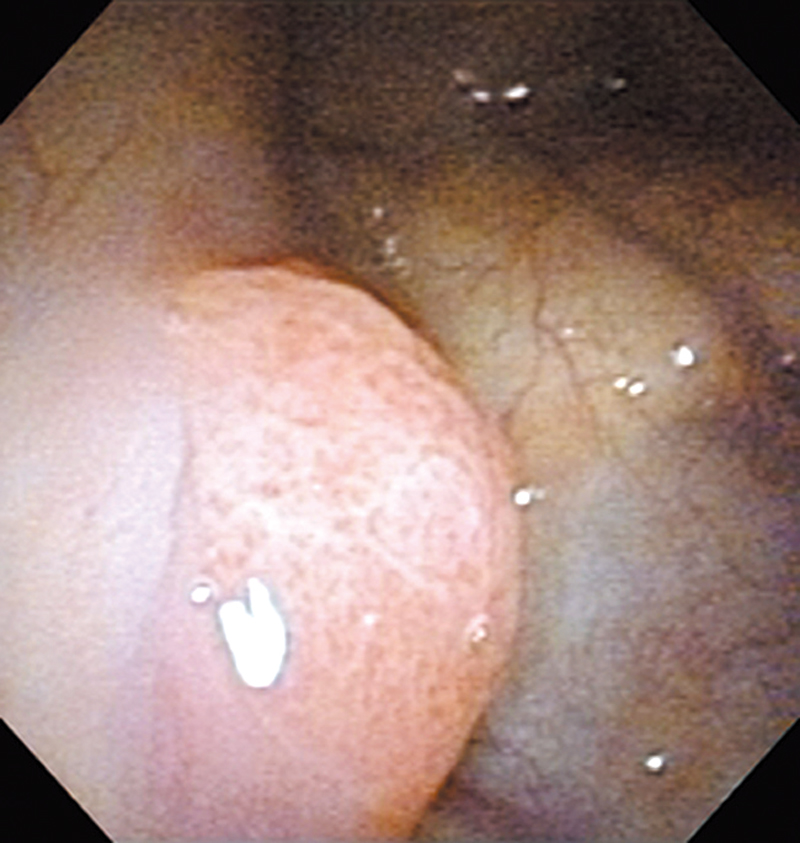

Hypopharynx Cancer (Left Pyriform Sinus: Elevated Type) Aged 80, male

white light

The patient visited us with a chief complaint of abnormal sensation in the pharynx and the elevated lesion was

detected on the left pyriform sinus in a laryngopharyngoscopic NBI examination.

The NBI image showed a brownish elevated lesion with scattered brown dots. In the conventional white light image, it was recognizable as a reddish elevated lesion.

The lesion was treated with endoscopic mucosal resection, and diagnosed as a squamous cell carcinoma in situ.